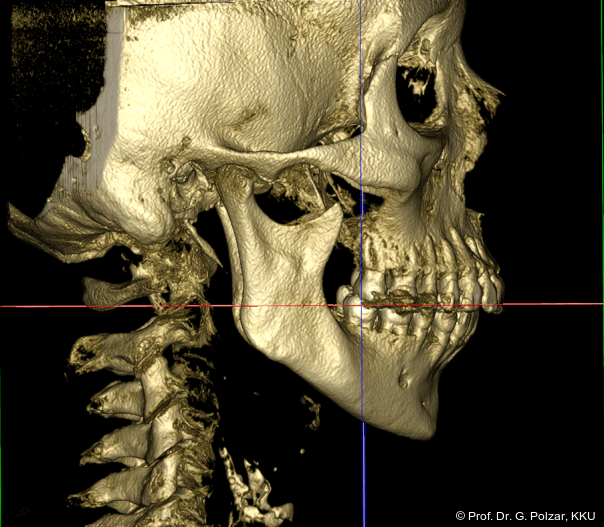

KG-Position: Die 3D-Ansicht im DVT zeigt eine vorverlagerte UK-Position bei neutraler Okklusion (Abb. 4a+b).

Diese deutlich anteriore Gelenkposition im Neutralbiss ließ den Verdacht auf einen Sunday Bite zu. Das heißt, die Patientin schob den Unterkiefer aktiv nach vorne, um damit schönere Schneidezahnkontakte bzw. eine vermeintlich neutrale Okklusion zu erreichen. Nach mühsamen Lockerungsübungen gelang es der Patientin, auch in die zen­trale Kiefergelenkposition zu wechseln. So zeigte sich das ganze Ausmaß der Malokklusion. In neutraler KG-Position hatte die Patientin eine sagittale Frontzahnstufe von ca. 7 mm mit 1 PB Klasse II-Okklusion im Seitenzahn­bereich (Abb.5a+b, 7a–c).

Beide Kiefergelenke (KG) befinden sich nun in zentraler Kondylen-/Fossa-Position bei neu­traler Okklusion (Abb. 10+11).

In der Frontalansicht ist eine leichte links-laterale Abweichung des Unterkiefers von der Schädelmitte zu erkennen (Abb. 29). Nach chirurgischer Analyse wurde die Laterognathie weitgehend ausgeglichen und der UK in CranioPlan zentrisch ausgerichtet (Abb. 30a–c).